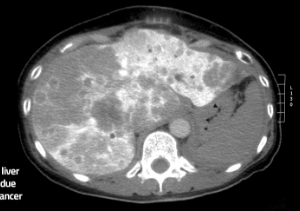

(COLO-MET) Novel mass spectrometry-based urine test for early detection of colorectal cancer metastases in the liver

The COLO-MET project aims to develop an easier, cost-effective and patient-friendly test, involving a urine test combined with a blood test, for early detection of liver metastases, which is associated with bowel cancer. The COLO-MET project will address an important clinical need for affordable, fast and patient-friendly colorectal carcinoma monitoring. The motivation for this work is to find molecular markers that can aid in simple diagnostics in cancer. The project started with a focus on metastsasis of corectal cancer because of its high social and economic impact. This project will be performed by a strong public-private consortium. Erasmus MC’s Dr. Theo Luider (project leader) will perform retrospective clinical validation of Host Cell Protien (HCP) biomarkers. In collaboration with the world-leader in laboratory equipment Thermo Fisher Scientific, Erasmus MC will optimise the innovative PRM analytical method to achieve high quantification precision and accuracy. Erasmus MC’s Prof. Jan IJzermans will collect patient samples and provide training sessions for clinicians. Students from the Biology and Medical Laboratory research programme of Rotterdam University of Applied Sciences will receive on-site training in mass spectrometry techniques, business development and bringing innovations from academia to the market.